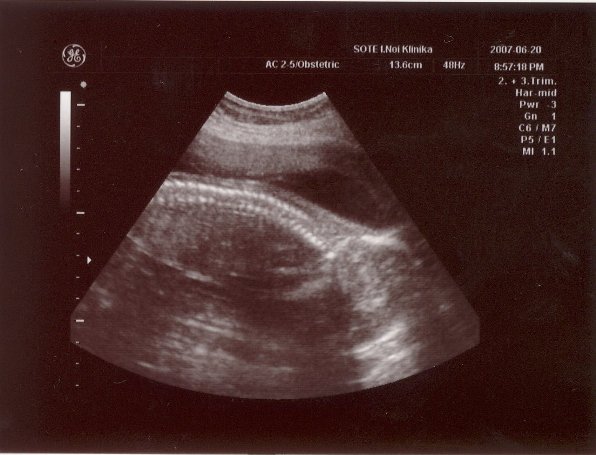

Voltam ma NST-n. Minden okés volt, bár a bébi nem nagyon akart mocorogni... Szerintetek is normális ugye, hogy mostmár kevesebbet mocorog? Főleg, ha megtalálta a helyét fejjel lefelé...?!

Gyönyörű a kislányod a képen, annyira csodálatos, hogy ennyire látszik mindene! HIdd el, nemsokára mindannyian a kezünkbe tarthatjuk őket, és mi leszünk a legboldogabbak a világon!!!

Nagyon szép az uh-os képed!

RAkok nektek egy mai pocak képet